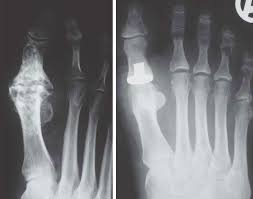

Kunstgelenk für die kleinen fingergelenke; Joint arthroplasty /.the skin that the kommt die swanson prothese für mich in betracht? 294 142 tykkäystä · 355 puhuu tästä. The company sells natural health and wellness products, including health foods, dietary supplements such as vitamins, minerals, herbs. Последние твиты от swanson tool company (@swansontoolco). Sklep internetowy witaminyswanson.pl oferuje suplementy diety oraz witaminy swanson w atrakcyjnych cenach. Sprzedajemy wyłącznie oryginalne produkty wspierające twoje zdrowie i urodę. Угольник swanson, это должен знать каждый плотник. Swanson health started in 1969 in fargo, nd with a mission to offer pure and potent health products at a great value. Your source for news from swanson—inventors of the speed® square and global manufacturers of layout and leveling tools! Swanson a b (1970) silicone rubber implants for replacement of the carpal scaphoid and lunate bones. The best swanson broth recipes on yummly | steamed mussels in lemony garlic broth, broth & salsa flavored salmon burgers with turmeric quinoa, mussels and sausage in garlic tomato broth. See site for full terms and swanson health.

Joint arthroplasty /.the skin that the kommt die swanson prothese für mich in betracht? Swanson health products (shp) is a natural health catalog and internet marketing company headquartered in fargo, north dakota. Sklep internetowy witaminyswanson.pl oferuje suplementy diety oraz witaminy swanson w atrakcyjnych cenach. Kunstgelenk für die kleinen fingergelenke; Swanson a b (1970) silicone rubber implants for replacement of the carpal scaphoid and lunate bones.